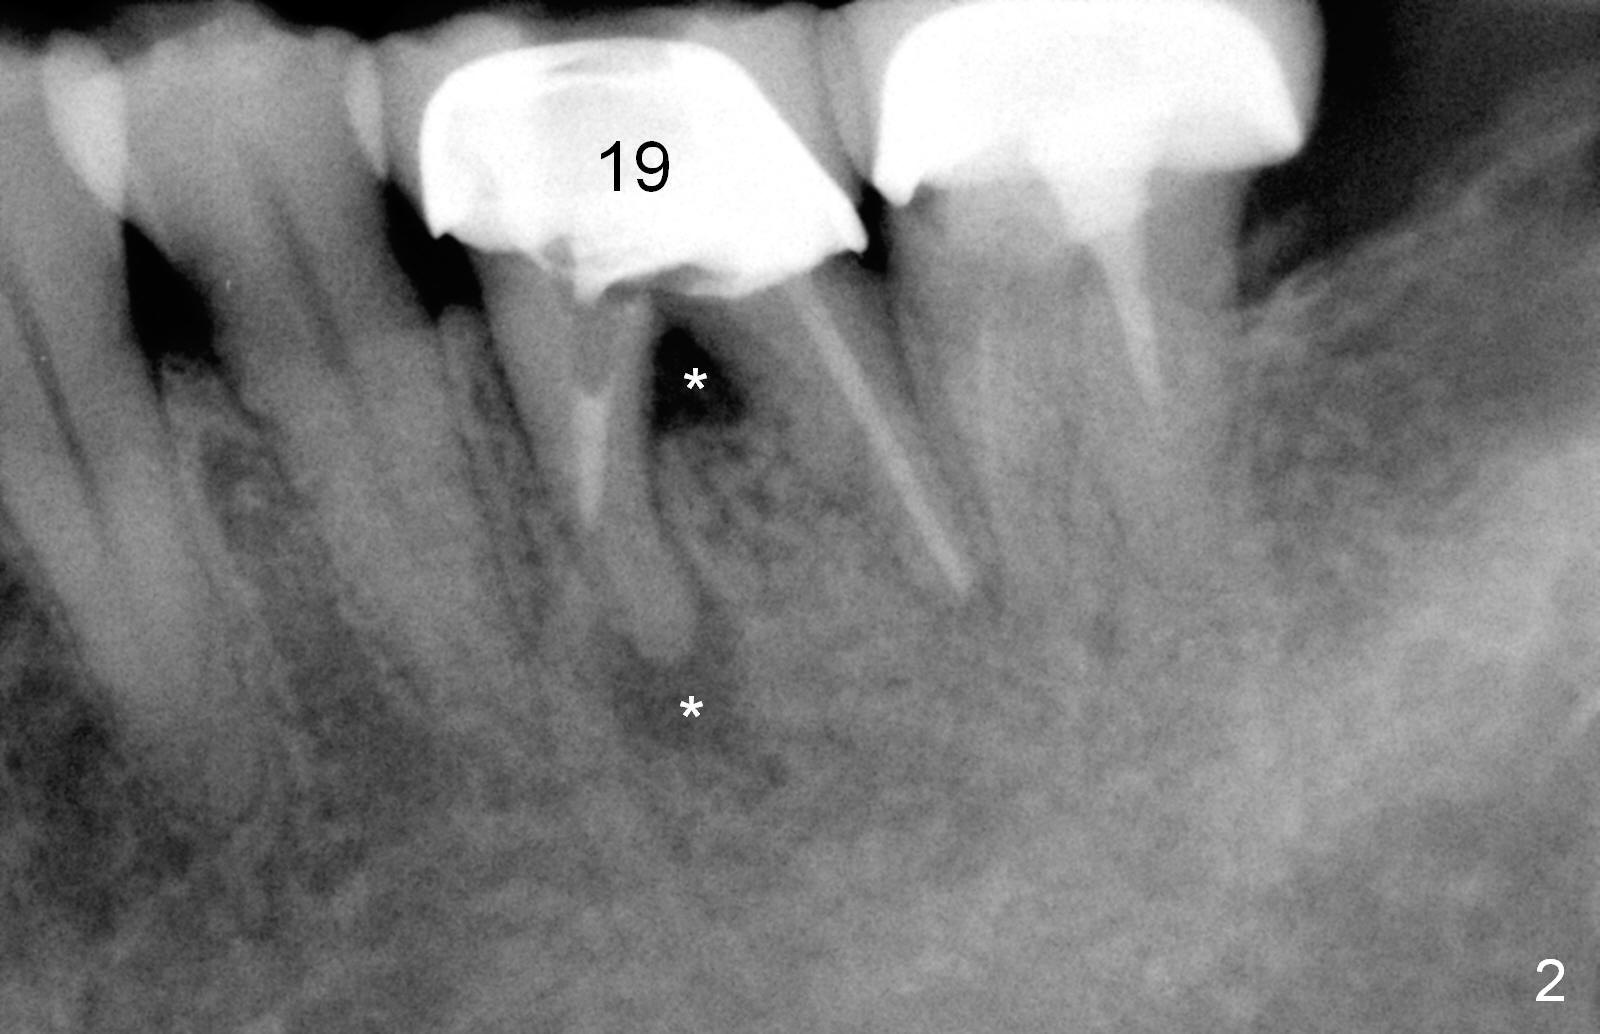

A 47-year-old lady lives out of town and presents to clinic with chief complaint "lower left back tooth easily bleeding with food impaction". Dental history and examination reveals failure of endo retreat of the tooth #19 (Fig.1), buccal gingival swelling (S), open access (A) and furcal and mesial periapical radiolucency (Fig.2 *). She is pleased to know availability of immediate implant and immediate provisional and accepts and receives the treatment at the same visit. The immediate implant (tissue-level) is designed to be as large as 7 mm and as long as 17 mm (Fig.3). To reduce paresthesia (yellow dashed line: the possible upper border of the Inferior Alveolar Canal)), a shorter implant (14 mm long in red line) is preferred. The tooth is extracted with sectioning. Granulation tissue is removed from the furca. The buccal plate appears to be intact. The septum is flat (Fig.4,10a S). Osteotomy starts in the middle of the septum with a 1.2 mm drill (Fig.10b red circle). As osteotomy increases in diameter (Fig.5 O), the apical end appears to be deviated mesiobuccally (Fig.10c large red circle). When a 6x17 mm tapered tap is being placed 14 mm deep (Fig.6 T), vibration of the buccal plate is seemingly felt at the apex (Fig.10d green circle). Further osteotomy may perforate the buccal plate. A 6x14 mm tissue-level implant is placed with >60 Ncm of insertion torque (Fig.7,8 I), followed by a 5x3 mm abutment (A) and bone graft (* in the remaining socket gap). An immediate provisional is cemented without occlusal contact (Fig.9 P).

Buccal gingival swelling and mesial periapical radiolucency suggests weakened buccal plate. Osteotomy in the septum should be initiated more lingually (Fig.10e). When the osteotomy starts being deviated, correct as early as possible with a Lindamann bur and preferably over-correct (Fig.10f blue circle). The final implant placement may not encroach the buccal plate (Fig.10f red circle). Three weeks postop, the buccal infection dissolves (Fig.11). What has not disappeared is the buccal undercut (*): the basis for potential buccal perforation. Buccolingual osteotomy trajectory should be adjusted intraoperatively accordingly.